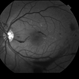

- anaemic retinopathy, vitreous hemorrhage

- Fundus camera

- Vitreous haemorrhage in a 25-year-old gentleman with severe anaemia and thrombocytopenia.